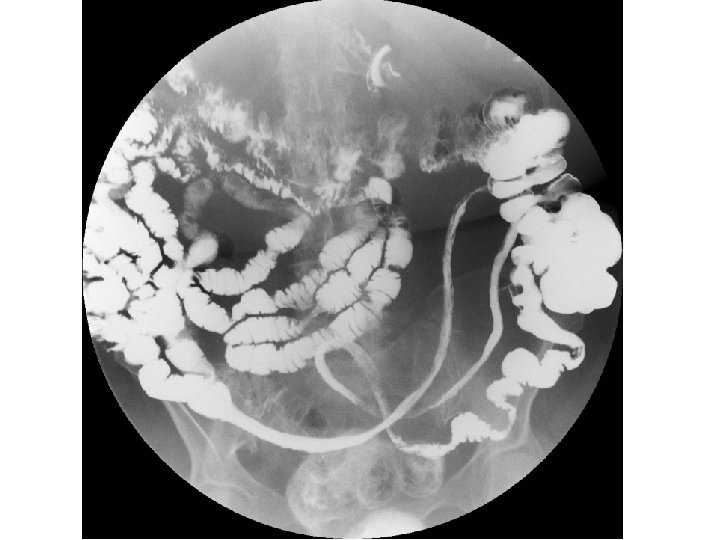

ESTUDIO BARITADO

Estudio baritado (I) • La distribución segmentaria coincidiendo con territorios vasculares concretos, con indemnidad de otros territorios, y el aspecto "en asa" (literalmente) en el caso delgado, con extensión de concavidad a concavidad, orientan al diagnóstico de isquemia crónica segmentaria cuando se realiza un estudio baritado.

Estudio baritado (I) • En nuestra paciente se daban estos hallazgos: – distribución segmentaria y única; – aspecto "en asa" con extensión de concavidad a concavidad; – preservación del íleon terminal.